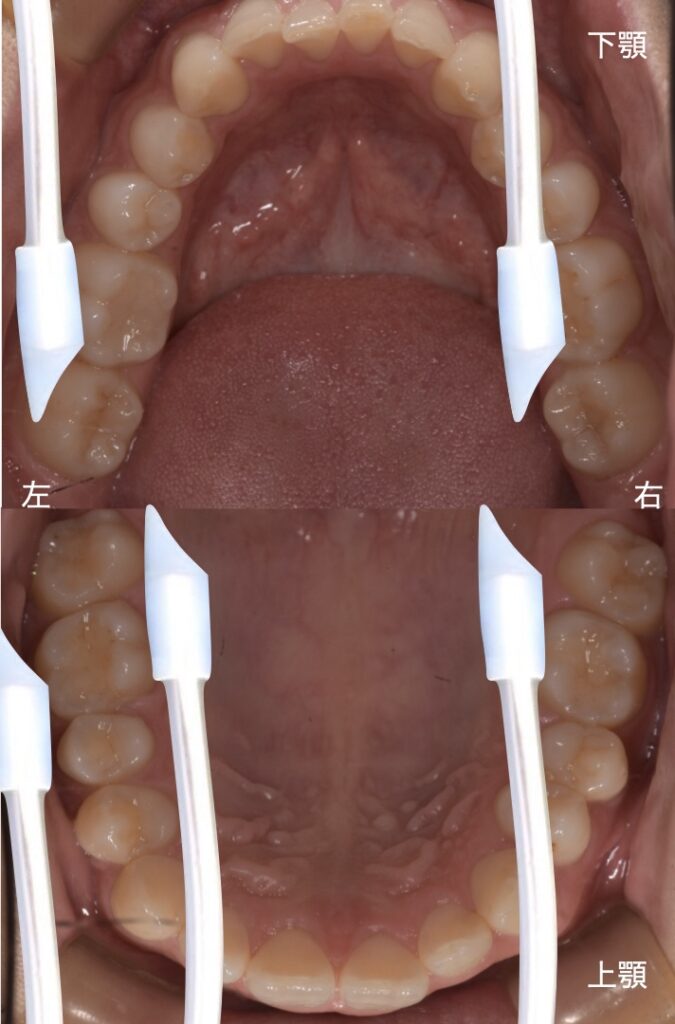

◆ 左サイドからの吸引

左側から吸引することが多く、

- 右下舌側

- 左下頬側

- 右上口蓋側

- 左上口蓋側

といったように、頬側から入れると治療がスムーズに進みます。